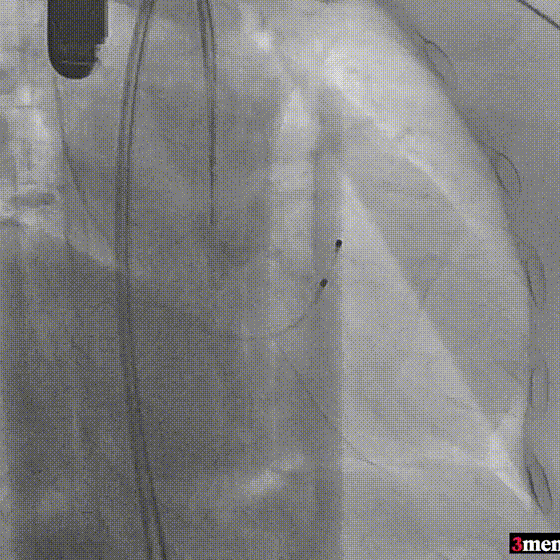

造影查看瓣膜形态

球囊后扩

最终造影

瓣膜释放后,超声提示患者存在一定的跨瓣压差和反流,通过球囊后扩,患者跨瓣压差即刻显著下降,反流量轻微。术后患者心功能持续得到改善,效果良好,此次手术取得圆满成功。